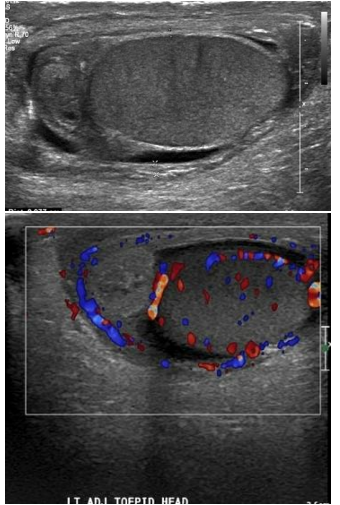

Você realiza na urgência o exame ultrassonográfico

de bolsa escrotal com doppler de adolescente do sexo

masculino de 16 anos com dor testicular aguda e

encontra as seguintes imagens. Assinale a alternativa

correta.